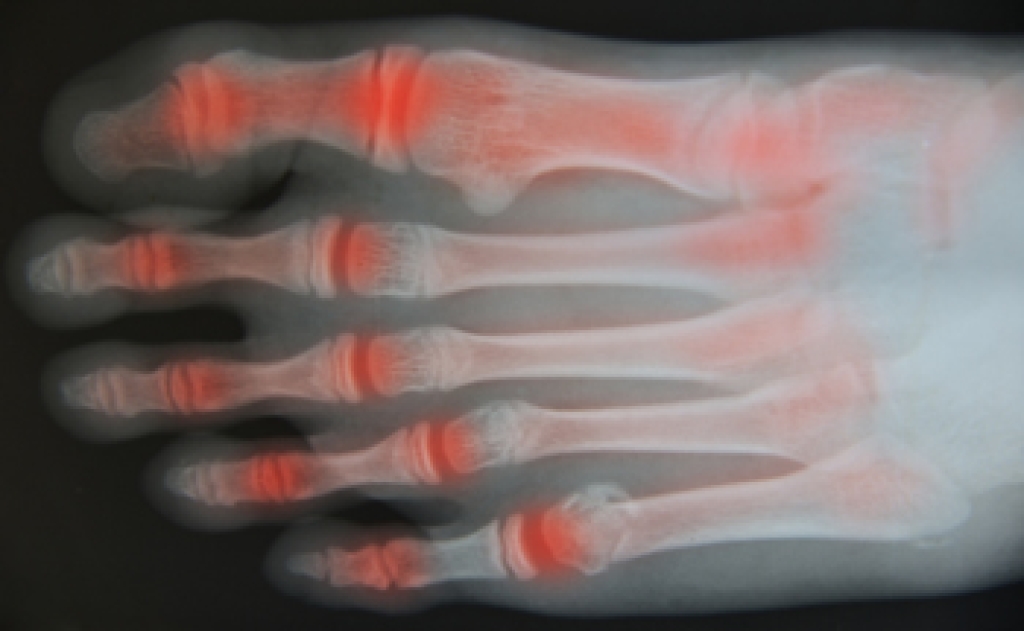

Joint pain may be common for those who participate in high intensity sports. It can be caused by injury to muscles, tendons, and ligaments. However, continued pain may be a sign that arthritis is developing. Though it is more common for one to get arthritis with age, it is also something that can gradually develop if repeated injuries happen and proper healing does not take place. There are different types of arthritis, and they fall into the two main categories known as inflammatory arthritis and osteoarthritis. Inflammatory arthritis results from a systemic disease where the body’s immune system attacks its own joints and tissues. Rheumatoid arthritis is an example of inflammatory arthritis, and is a symmetrical problem that affects both sides of the body at the same time. Osteoarthritis is a degenerative ailment that comes from wear and tear on joints over time. This is a typical type of arthritis that can affect the big toe. If you are experiencing joint pain in your feet, it is suggested that you contact a podiatrist who can properly diagnose whether arthritis is the cause and offer treatment options.

Arthritis is a joint disorder that involves the inflammation of different joints in your body, such as those in your feet. Arthritis is often caused by a degenerative joint disease and causes mild to severe pain in all affected areas. In addition to this, swelling and stiffness in the affected joints can also be a common symptom of arthritis.